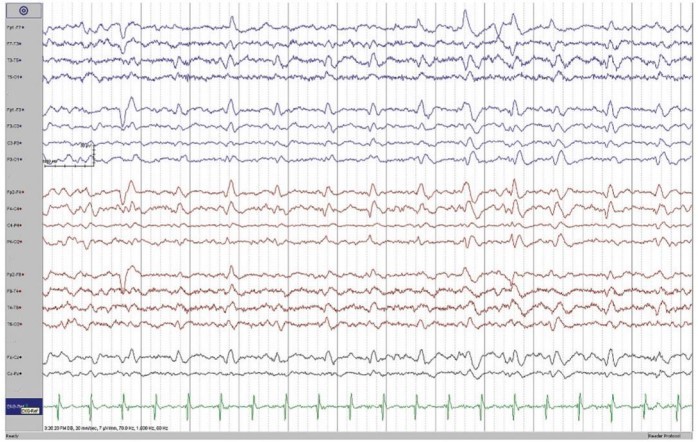

EEG reveals the presence of periodic sharp wave complexes (bi-phasic or triphasic) occurring at a frequency of about 1Hz.

A brain MRI of the patient revealed a cortical-ribboning pattern with mild asymmetry and left caudate head hyperintensity. EEG showed intermittent sharp-wave complexes which were quasi-periodic along with slowing of background activity. Other routine blood biochemical tests were normal; lumbar puncture was not done as consent was not obtained.

EEG features comprising periodic spike and wave complexes can also be seen in Hashimoto’s Encephalopathy, Lewy Body Disease and Hepatic Encephalopathy. Some other disorders which present with rapid cognitive decline like sCJD include paraneoplastic and autoimmune limbic encephalopathies, neoplasms, CNS vasculitis & metabolic and toxic encephalopathies. These must be thoroughly ruled out before considering a diagnosis of sCJD.